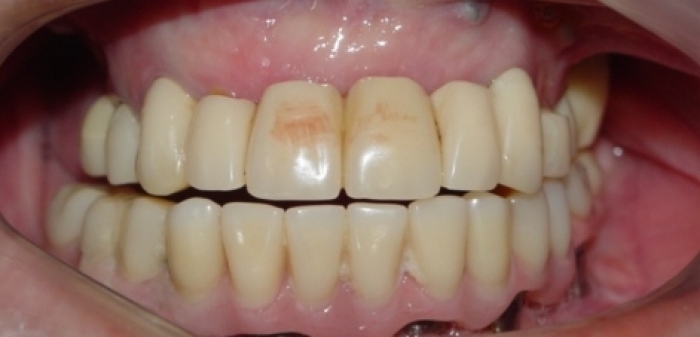

Imagem Próteses Provisórias Fixas Superior e Inferior , em 2011 - Clínica Cliniface

Imagem Próteses Provisórias Fixas Superior e Inferior , em 2011